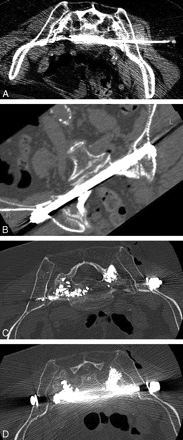

On neurologic examination, the patient was 157.5 cm (62 inches) and weighed 59 kg (131 lb). Neurologic examination was within normal limits. CT images of the lumbosacral spine demonstrated severe osteoporosis, sacroiliac joint incompetence, and bilateral comminuted fractures of the sacrum and pelvis (Fig 1). There was concern that lone sacroplasty would not provide adequate stabilization of her SIFs, and thus CT fluoroscopically guided percutaneous placement of a transiliosacral rod combined with sacroplasty was recommended. We discussed the potential risks and benefits of the procedure with the patient, as well as the options of lone sacroplasty and conservative medical management. After lengthy discussion, the patient agreed to undergo the proposed procedure.

Axial CT image of the sacrum showing severe osteoporosis and bilateral comminuted fractures of the sacral alae.

Axial CT images of the sacrum during placement of vertebroplasty needle (A), after placement of transiliosacral rod (B), and after sacroplasty (C,D).